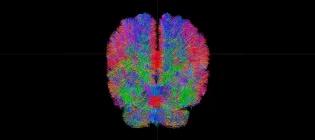

Over 1,200 staff and students collaborate across our core research areas, bringing together expertise that spans the body and life course. As part of driving progress in our core research areas, we host several leading research centres and house state-of-the-art technologies, which you can explore on this page. Want an introduction to our research first? Visit our Research page Explore the centres and units within our institute Anne Rowling Regenerative Neurology Clinic A globally leading, patient-centred, integrated care-research facility. The Clinic seamlessly integrates the best NHS health care with the best University health research, as key to discovering and trialling new treatments for neurological conditions. Euan MacDonald Centre for Motor Neuron Disease Research Pioneering vital research into motor neuron disease and unitiing over 300 scientists, doctors and healthcare professionals across Scotland, this centre is home to Europe’s largest clinical drugs trial for MND, MND-SMART. Jennifer Brown Research Laboratory A group working to improve understanding of what causes early labour, how we can develop treatments to prevent it and how we can better help newborn babies in those first crucial hours and days after birth. Muir Maxwell Epilepsy Centre A centre dedicated to investigating the causes of childhood-onset epilepsy. Simons Initiative for the Developing Brain Discovering the biological mechanisms underlying neurodevelopmental disorders - a research centre bringing together research groups across multiple sites. UKRI Mental Health Platform A network of researchers with the shared aim of accelerating research into severe mental illness and improving the diagnosis and treatment of those affected. British Heart Foundation Centre of Research Excellence A world-leading centre of excellence working to improve lives for people with cardiovascular, neurovascular, or metabolic health conditions. Edinburgh Clinical Research Facility State of the art facilities to support multidisciplinary clinical research locally, nationally and internationally. MRC/BHF Centre of Research Excellence in Advanced Cardiac Therapies (REACT) REACT unites academic, healthcare, industry and public partners to develop innovative DNA and RNA-based therapies capable of regenerating injured hearts and reversing established damage. It is co-led by King’s College London, the University of Edinburgh and the University of Oxford. Patrick Wild Centre A research centre that aims to better understand genetic conditions affecting brain development, and to improve the care and treatment available for people with these conditions. UK Dementia Research Institute at Edinburgh A centre of excellence that aims to elucidate the interactions within and between the brain vasculature, neurons, macroglia and microglia which control the trajectory of neurodegenerative disorders leading to dementia, and exploit this knowledge for therapeutic benefit. Centre for Pesticide Suicide Prevention A research and policy initiative working to reduce the number of pesticide suicides worldwide. Edinburgh Imaging World class imaging for research and diagnostic needs, working with academic researchers, NHS clinicians and commercial imaging organisations, including biotech, pharmaceutical & private medical industries. MS Society Edinburgh Centre for MS Research A multidisciplinary centre-without-walls funded by the MS Society, dedicated to laboratory, translational and clinical research into multiple sclerosis. Row Fogo Centre for Research into Ageing and the Brain Researchers working together to improve the understanding of how blood vessel diseases can damage the brain, leading to stroke, cognitive decline, dementia and mobility problems. UKRI Hub for Metabolic Psychiatry Part of the Mental Health Platform, this Hub brings together six interdisciplinary workstreams operating in concert to advance our understanding of the connection between metabolic and mental health. This article was published on 2026-03-17